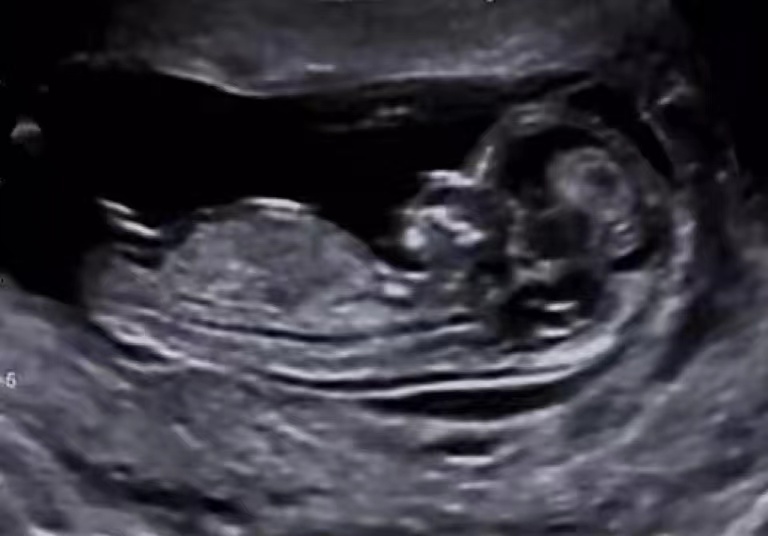

【健康科普】孕妇彩超检查小妙招

彩超检查是孕妇不可缺少的检查项目,从早孕到产后,及时检测胎儿发育及母亲的身体情况。有哪些小妙招可以让我们的彩超检查更顺利呢?适度充盈膀胱:可以推开肠道气体,显示孕囊及...